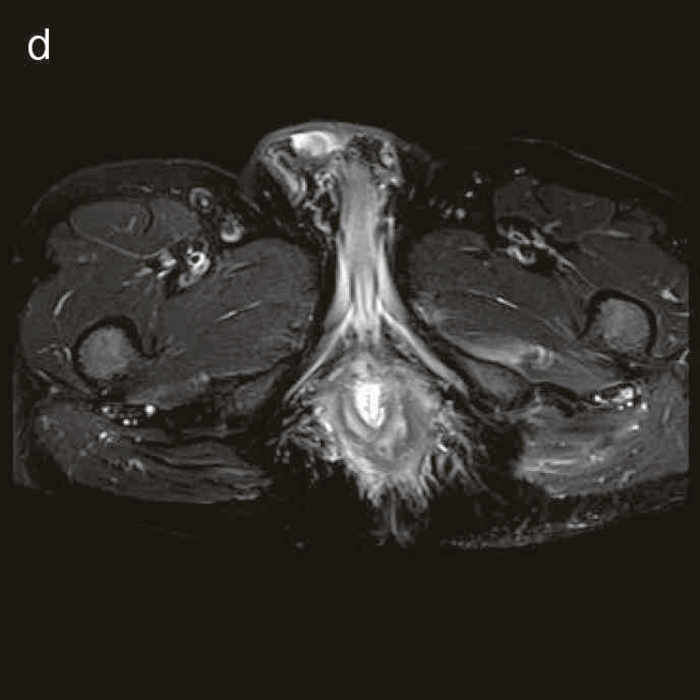

図27 CD直腸肛門部癌の骨盤造影MRI検査像

直腸内に増強効果を受ける分葉状の腫瘤を認める。

精査で施行したCT,MRIで痔瘻癌が疑われた。

診断時のMRIでは直腸下部壁内から周囲にhigh intensity areaが拡がり,右側には痔瘻の瘻管を認めた。high intensity areaは前方で前立腺や陰茎海綿体付近まで広がっていた。